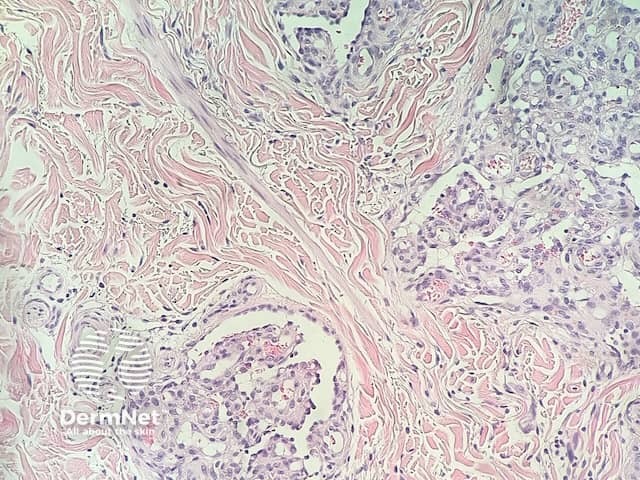

In glomeruloid haemangioma, the histopathology shows numerous dermal ectatic vascular spaces lined by flat endothelial cells. Inside these dilated vascular spaces are a conglomeration of capillaries lined by plump, swollen endothelial cells, filled with red blood cells, resembling renal glomeruli (figures 1–4).